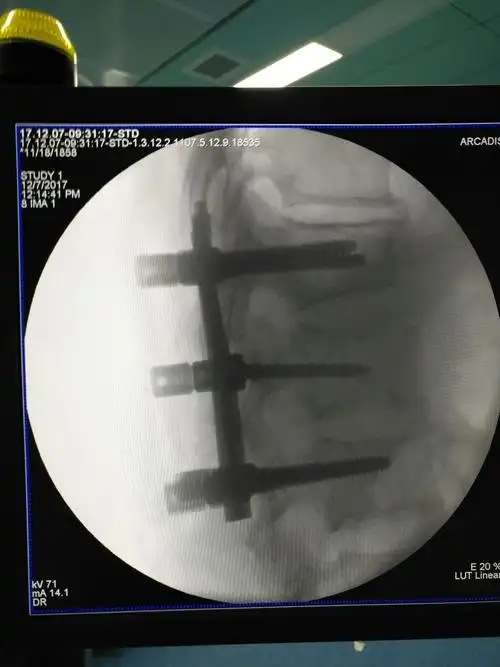

腰椎钉棒固定 减压术